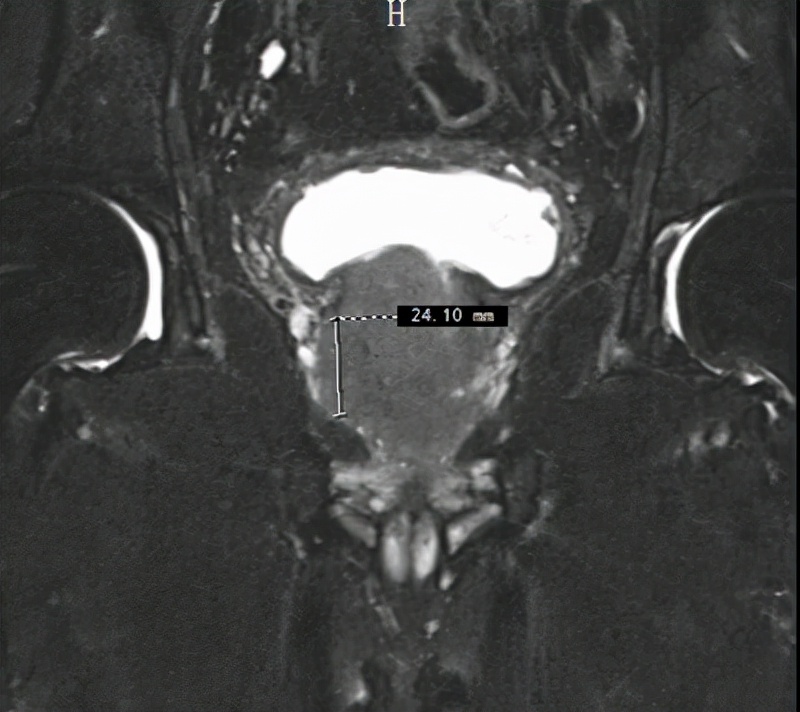

据了解,任爷爷9月下旬到十堰人医做健康体检,经磁共振检查提示前列腺结节,同时前列腺总特异性抗原(TPSA)异常升高,10月3日收治于该院泌尿外科一病区,经进一步穿刺活检,确诊为高危前列腺癌。

患者术前影像资料

十堰人医泌尿系统疾病中心常务副主任李云飞博士介绍,前列腺癌是中老年男性最为常见的恶性肿瘤之一,临床上对局限性前列腺癌分为低危、中危及高危三个层次,任爷爷的情况处于最高危,有扩散转移风险。同时任爷爷前列腺增生明显,严重影响到正常排尿,生活质量受到较大影响。